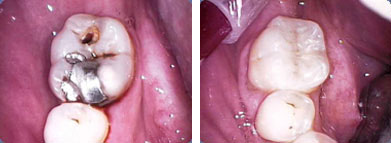

" ...wenn der Zahn aber nun ein Loch hat ..." dann ist eine Füllung unumgänglich. Dies wird entweder vom Zahnarzt direkt im Mund des Patienten angefertigt oder nach einem Abdruck vom Zahntechniker im Labor hergestellt (Inlay).